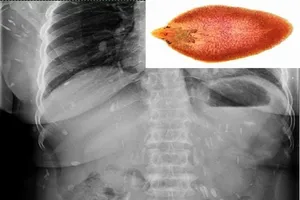

Theo hướng dẫn của Bộ Y tế, bệnh sán lá gan lớn là bệnh ký sinh trùng do một số loài sán lá gan thuộc họ Fasciolidae gây nên những tổn thương, những ổ áp xe tại gan hoặc một số cơ quan khác khi ký sinh lạc chỗ.

Người mắc bệnh sán lá gan do ăn sống các loại rau thủy sinh như: rau ngổ, rau muống, rau rút, rau cần, rau cải xoong, ngó sen... hoặc uống nước có nhiễm ấu trùng sán lá gan lớn.

| Ăn các loại rau thủy sinh như cải xoong, rau cần, rau rút (nhút) có nguy cơ cao mắc các bệnh do sán lá gan lớn. Ảnh: T.H |